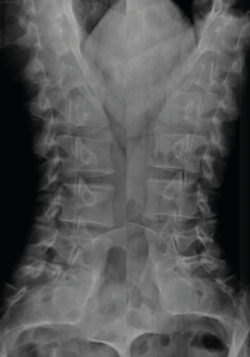

Radiografía simple de columna lumbar

Los estudios radiológicos simples son fáciles de obtener, están al alcance de la mayoría de los médicos y centros asistenciales, y son económicamente asequibles, sobre todo en comparación con otras técnicas diagnósticas. Como consecuencia de ello, teniendo en cuenta la elevada incidencia de dolor lumbar, es considerado el síntoma que determina con mayor frecuencia la solicitud de radiografías entre los pacientes no ingresados. Sin embargo, las diferentes revisiones sobre el tema y la opinión de los expertos en la materia abogan por limitar su uso a pacientes concretos y a un pequeño número de proyecciones(19).

Proyecciones radiológicas

La más frecuentemente utilizadas son la proyección AP y L. Se debe procurar incluir al menos hasta T11 y el borde superior de las caderas (Figura 8).

Las radiografías oblicuas no son necesarias de forma rutinaria, estando indicadas en pacientes con una elevada sospecha de presentar una espondilólisis (Figura 9).

Figura 9. Radiografías oblicuas de columna.

Las radiografías dinámicas, habitualmente empleadas para descartar la presencia de una inestabilidad vertebral, no deben realizarse nunca en la fase aguda del dolor lumbar.